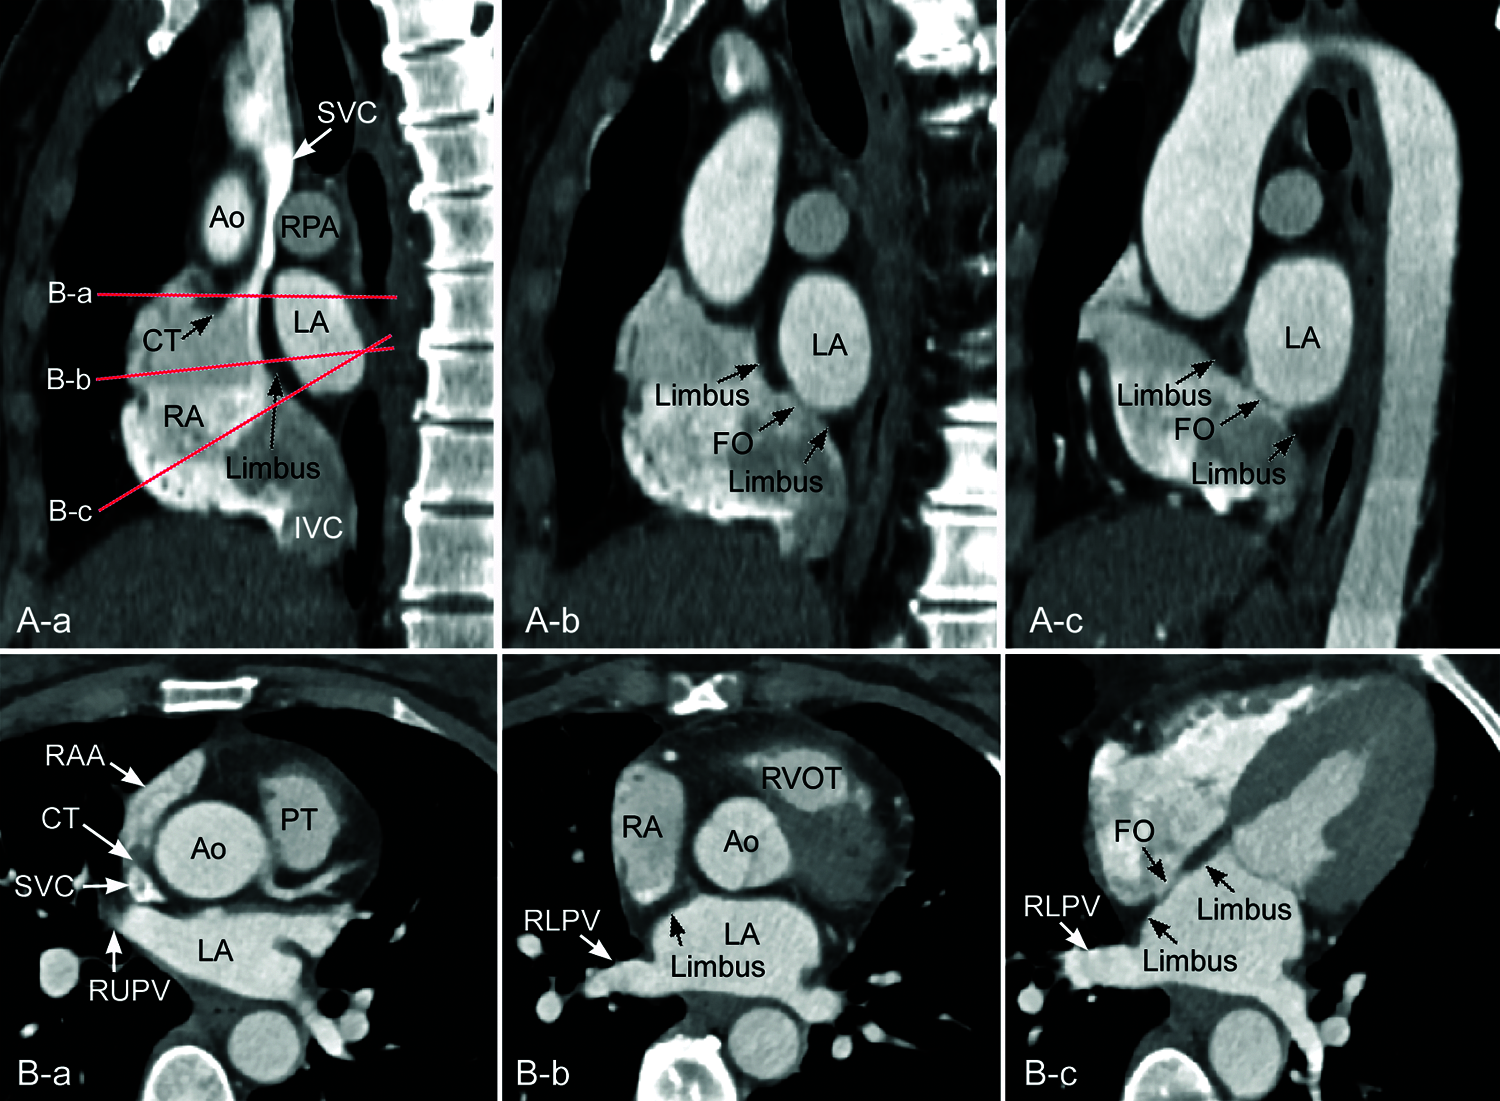

Figure 3: Computed tomographic angiograms from a mildly obese individual. A. Reconstructed images in parasagittal planes along the interatrial party wall. B. Oblique axial images reconstructed along the planes indicated in A-a. The limbus is prominent superiorly and far less prominent inferiorly in A-b and A-c. Note that the interatrial party wall through the central fossa ovalis (FO) in A-c is flat, while the party wall between the sinus venarum and the left atrium in A-a is convex forward and downward. The long axis of the inferior vena cava (IVC) is aligned superiorly to the left atrium (LA). Ao, aorta; IVC, inferior vena cava; CT, crista terminalis; LV, left ventricle; PT, pulmonary arterial trunk; RA, right atrium; RAA, right atrial appendage; RLPV, right lower pulmonary vein; RPA, right pulmonary artery; RV, right ventricle, RVOT, right ventricular outflow tract; RUPV, right upper pulmonary vein; SVC, superior vena cava